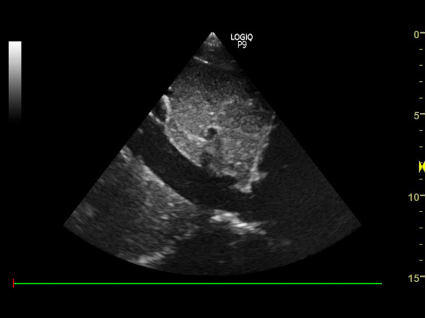

1) Subcostalt 4-kammer billede:

- Nævn strukturerne:

proben skal pege mod patientens ve. side